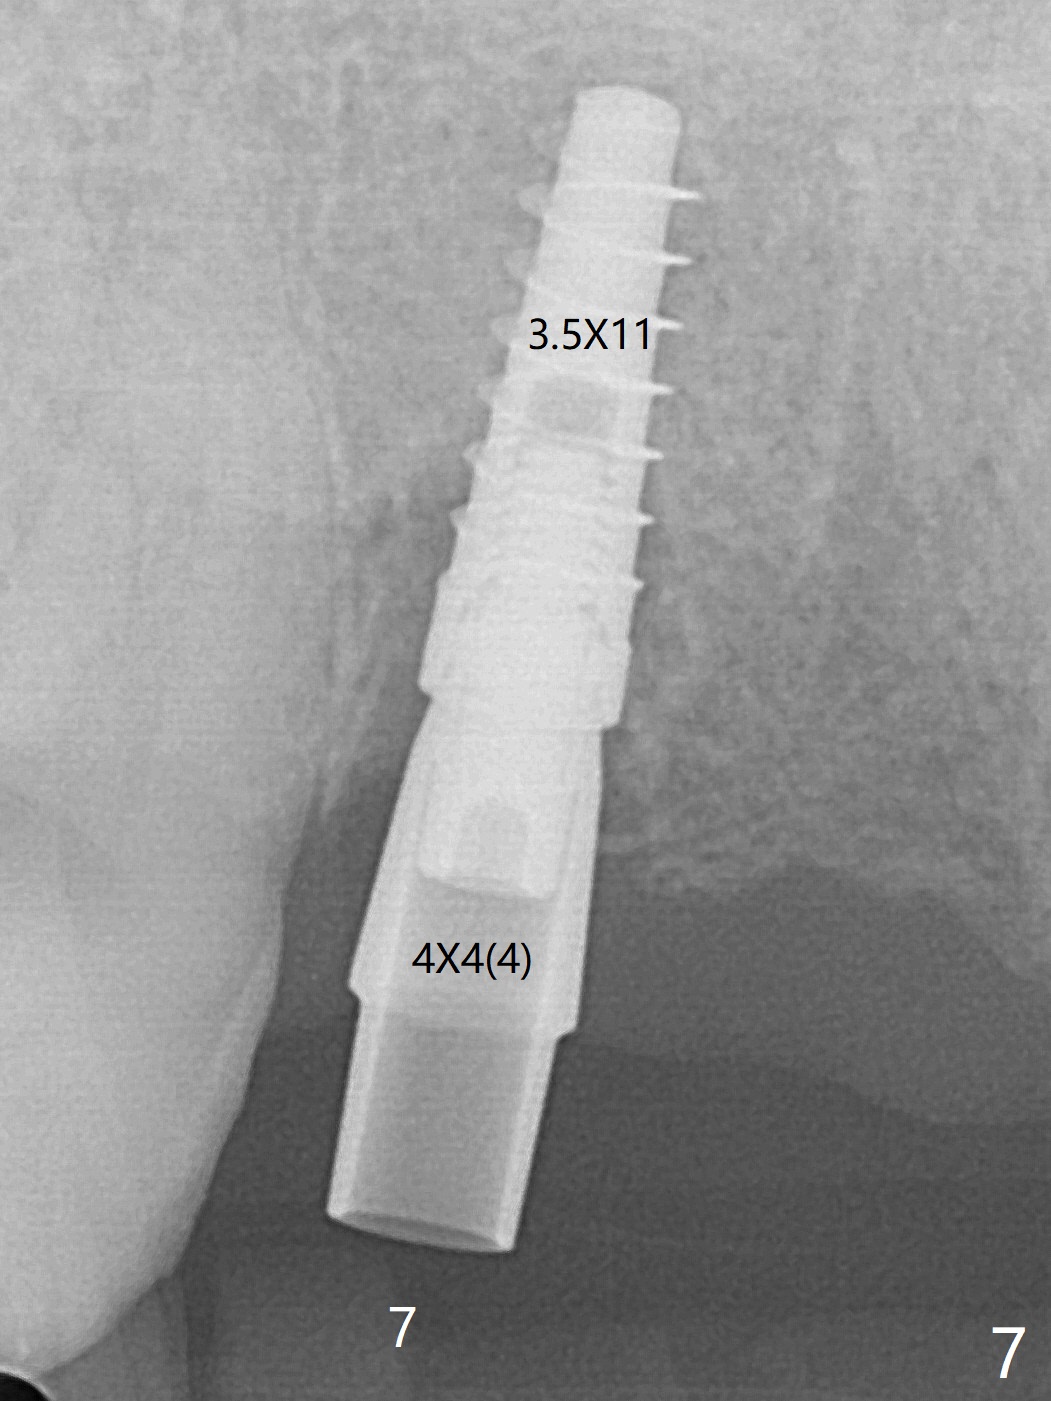

今天下午进入治疗室,粘性骨粉已制备:上清液来自红管(含促凝剂),离心3分钟(图一);再离心10分钟上清液就转变PRF,压制后,使用前剪成三块(图二:黑线),其中两块punch一个洞(图二:圆圈),插入7,9号牙基台固定;大块覆盖11/12号牙牙槽窝(图十四)。7,9,11,12号牙必须拔除(图三),然后在7,9,12种植。由于缺失左下磨牙,前牙垂直距离减少(图四)。完成9号牙位钻洞后,利用fixture mount(图五:M)植入植体,并留在原位固定导板(图六),然后7号牙种植,也留下fixture mount(图六:7,9),最后完成12号牙植入,但是后者扭力低,放置愈合螺帽(图九),而7,9号牙位放置修复基台(图七,八(使用5.5毫米profile drill后),好像基台没有完全就位。7号牙位更换基台似乎没帮助(图十),9号牙位再次放置同一个基台临床上仿佛有改变(比较图八与十二)。放置粘性骨粉后(图十一至十三),牙槽窝口覆盖PRF膜(图十四:P(A:基台)),最后使用树脂敷料固定骨粉和膜(图十五,六),基台帮助敷料固位,没有咬合干扰(图十七:*)。树脂敷料部分解决美观问题,一个月后撤除,如果植体仍有稳定性,可能制作7-10临时牙桥,可能部分维持或者恢复牙龈外形。术后一周病人主诉后面植牙和鼻底疼痛,11号牙根尖牙龈充血(图十八),轻度触痛,可能与术中尚未完全清创有关(图十九(术前CT 3D图像))。再服用Amoxicillin一周,症状好转,鼻底轻度触痛(图二十)。术后1.5月没有任何不适,撤除树脂敷料,7号牙基台(袖)显得太长,换一个短的(4.5x4(5)(图十,十一)->4x4(3)毫米)毫米),植骨好像愈合正常(图二十一:*)。7号牙换了短的基台,9号牙基台高度调整后,与对合牙有足够空间做临时牙桥,最好8,10号牙位牙龈应该凹陷(图二十二:*),有pontic外形。另外9号牙基台颊侧牙龈边缘有所修整,临时牙桥准备。先做7-10临时牙桥,理想临时牙桥pontic处树脂应该多些(图二十三:白线)压迫牙龈形成凹陷。11,12号牙牙槽窝在树脂(Bosworth)敷料下也正常愈合(图二十四)。